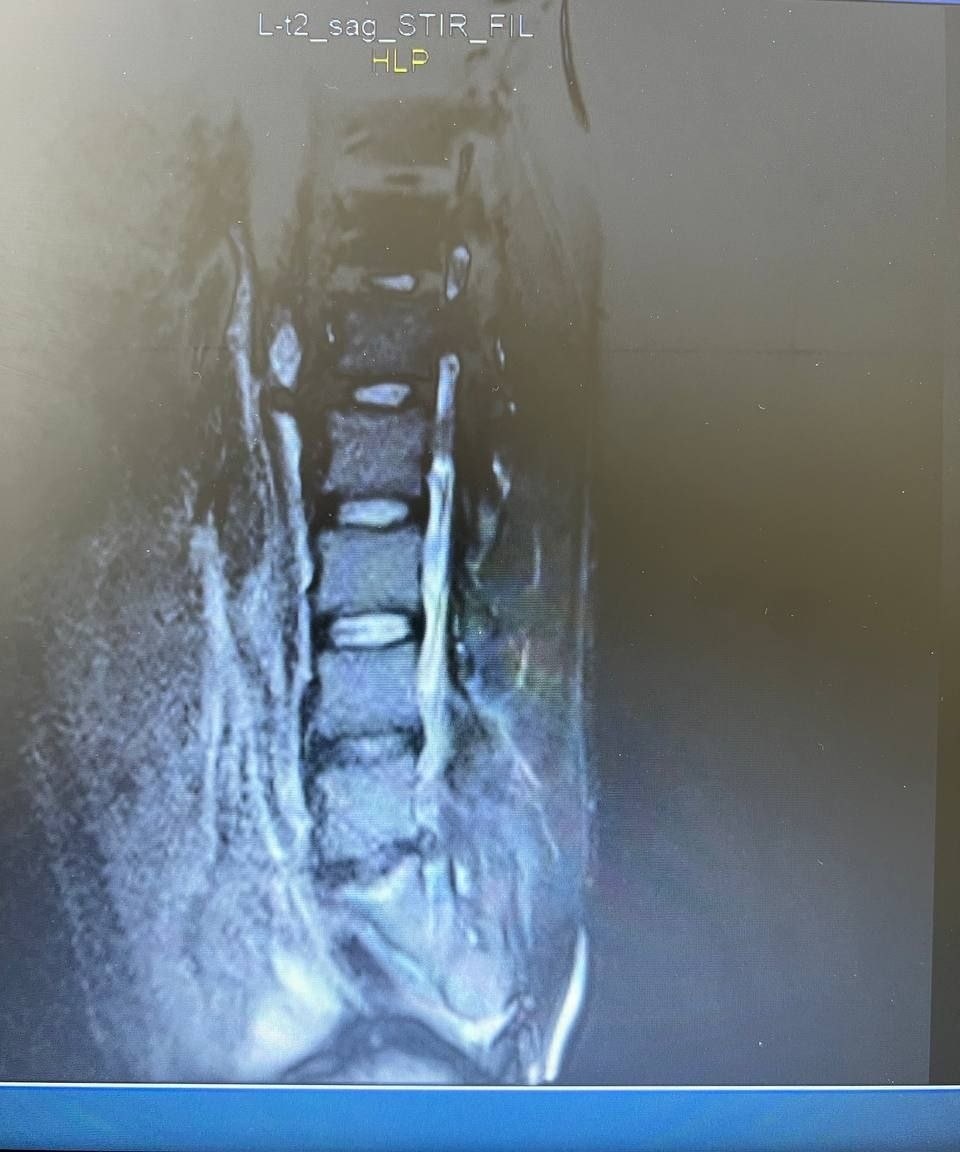

👉 Поэтому первое правило - диагностика. Отправил пациента на МРТ. И вот что показало обследование: грыжа L5-S1, воспалительный процесс, поражающий и разрушающий позвонки, острая стадия.

Результат можно увидеть на фото📷